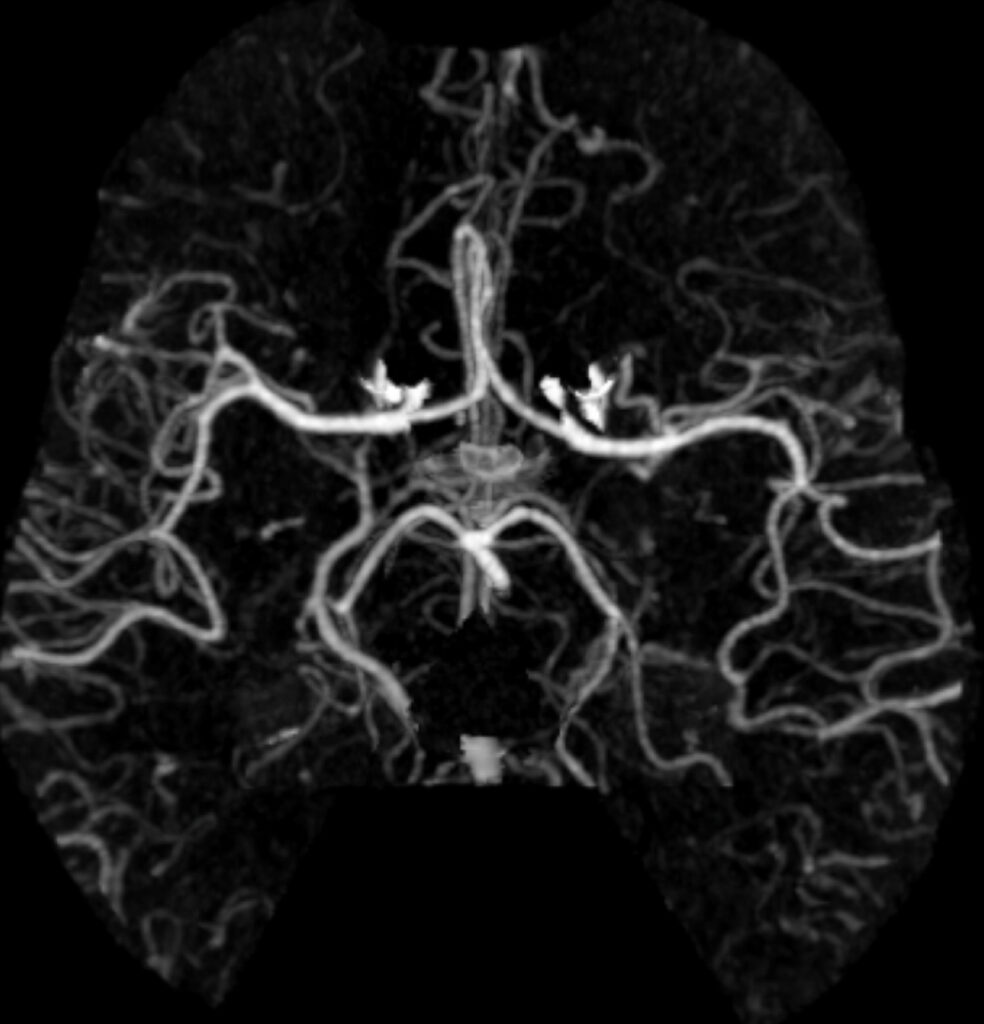

What abnormalities if any can you see?